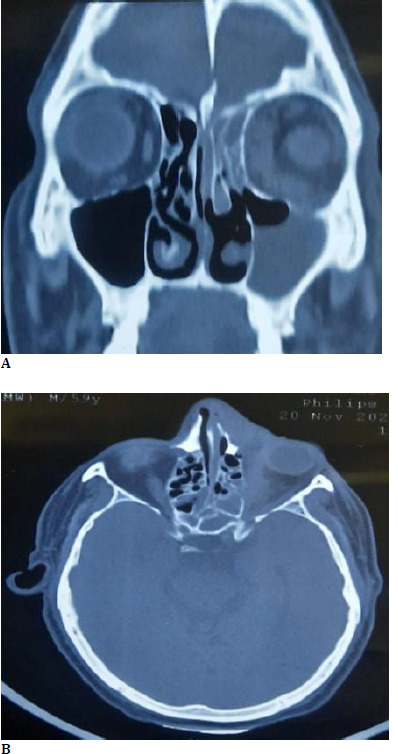

Mucormycosis is an aggressive, life-threatening fungal infection predominantly affecting immunocompromised individuals. It typically manifests as rhino-orbital or rhino-cerebral disease. However, rarely, its initial presentation may closely resemble an innocuous condition like acute dacryocystitis, which is prone to result in higher morbidity rates. Herein, we report a case of a 52-year-old diabetic patient who presented with symptoms suggestive of acute dacryocystitis. Broad-spectrum antibiotics were started, but the patient did not improve with therapy. Further investigations, including imaging and biopsy, unraveled invasive mucormycosis. Prompt surgical debridement and antifungal therapy were initiated, but the delayed diagnosis culminated in significant orbital involvement. A high index of clinical suspicion is warranted for mucormycosis in patients with risk factors such as diabetes or immunosuppression who present with dacryocystitis and are unresponsive to standard treatment. Early diagnosis and aggressive intervention play a pivotal role in improving patient outcomes in this condition.